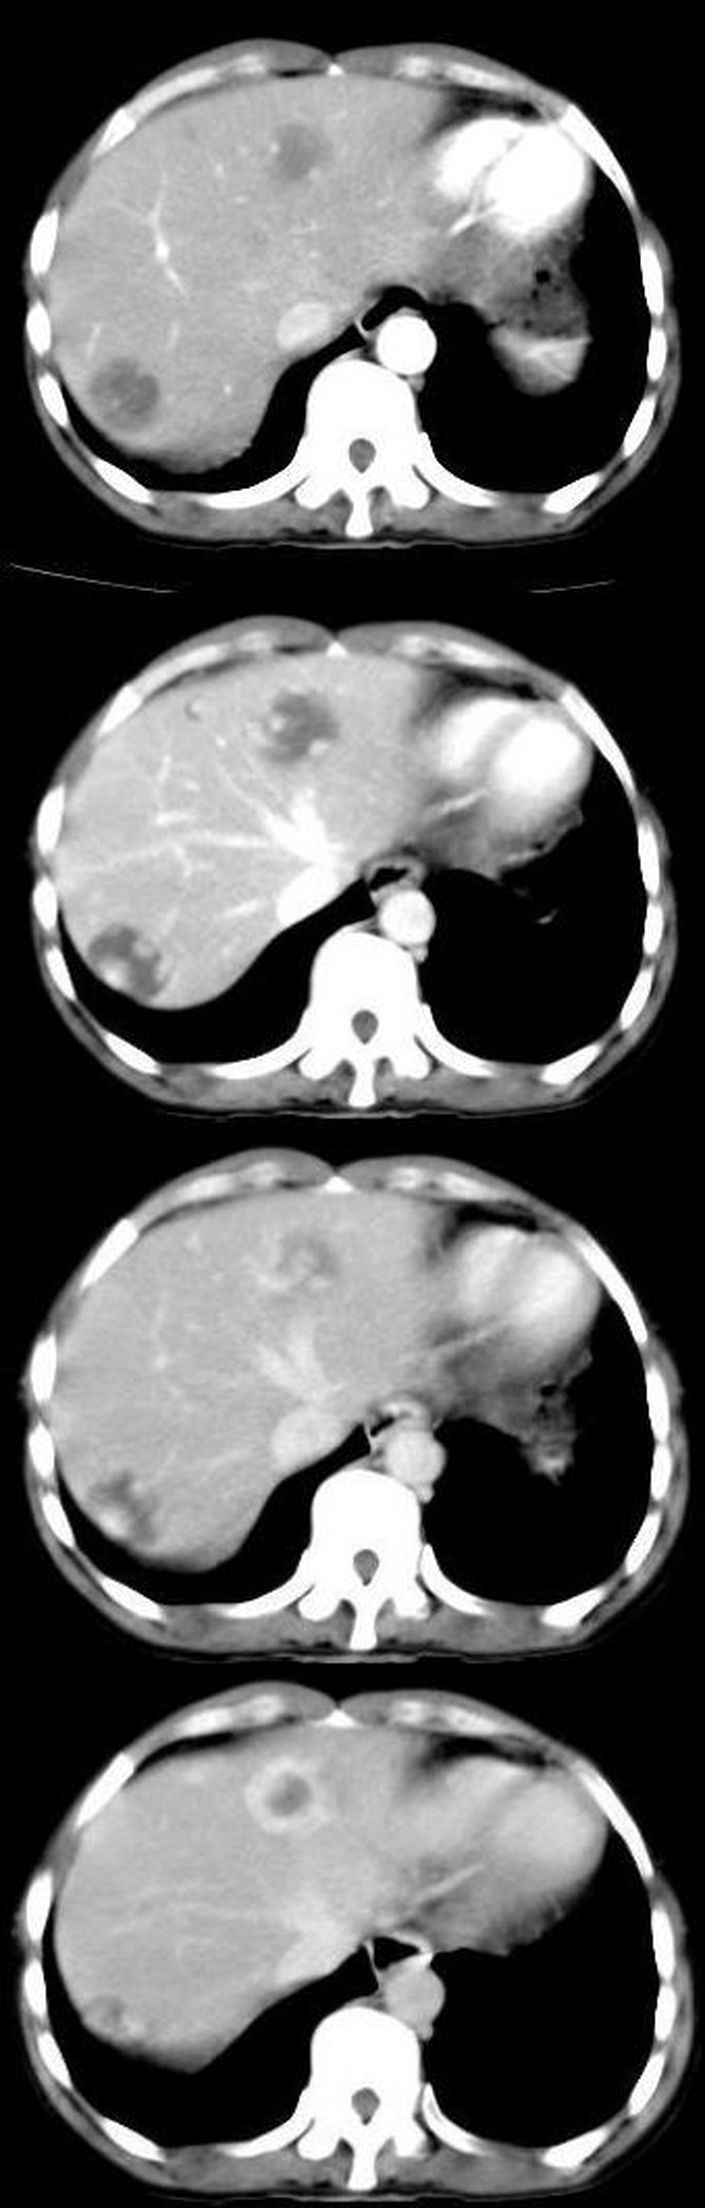

为了引起战友们的注意,我特意把典型的几个层面发表在这里,上两个是平扫,病灶密度较低,边缘较清楚,增强分别是动脉期,门脉期,延迟后4分钟和7分钟后的图片,讨论一下看,到底是什么性质的病变?

肝转移瘤也可出现类似肝血管瘤ct增强表现,既然升结肠ca可定,那么本例肝脏改变肝转移瘤首选,建议mri检查。

本例的困惑是延迟后强化更明显

我不是高手,不过我认为本例的牛眼征还是较典型的,所以考虑为转移。

支持肝脏多发转移瘤,(体现了肝动脉及门静脉双重供血之特点)

本人个子不高,我考虑肝左叶为血管瘤,肝右后叶为转移瘤。

牛眼征;边缘环壮强化;象转移瘤

转移瘤动脉期不会出现边缘结节状血管样强化,延迟扫描血管瘤和转移瘤都可以出现环状显著强化,二者病灶中心都可以出现坏死。故动脉期为主要鉴别依据。若再行延迟扫描(15分钟后)对二者的鉴别应该也有帮助。我认为是典型的血管瘤。

肝脏血管瘤可能性大,增强早期明显呈结节状强化,而延时扫描呈环状强化,但有可能延时不够或中间有坏死区.